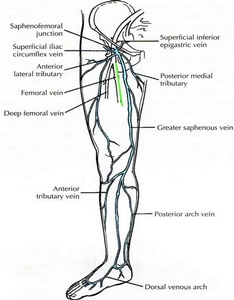

根據調查統計, 約有百分之25的女性, 和百分之18的男性, 罹患嚴重程度不等的靜脈曲張(varicose vein, vein reflux), 屬於慢性的文明病. 靜脈一般而言分成三種; 第一種乃深層靜脈(deep veins), 位於肌肉和纖維組織之間, 負責的靜脈血(也就是缺氧血, deoxygenated blood)的回流至心臟; 第二種是表淺靜脈(superficial veins), 位置在皮膚表層, 功能在收集表淺的血液; 第三種是穿透靜脈(perforator veins), 乃連接前兩種靜脈, 負責把表淺靜脈的血液帶到深層靜脈裏. 它的功能主要是把缺氧血帶回心臟

左圖可以知道各種靜脈的發生位置與相關

左圖可以知道各種靜脈的發生位置與相關